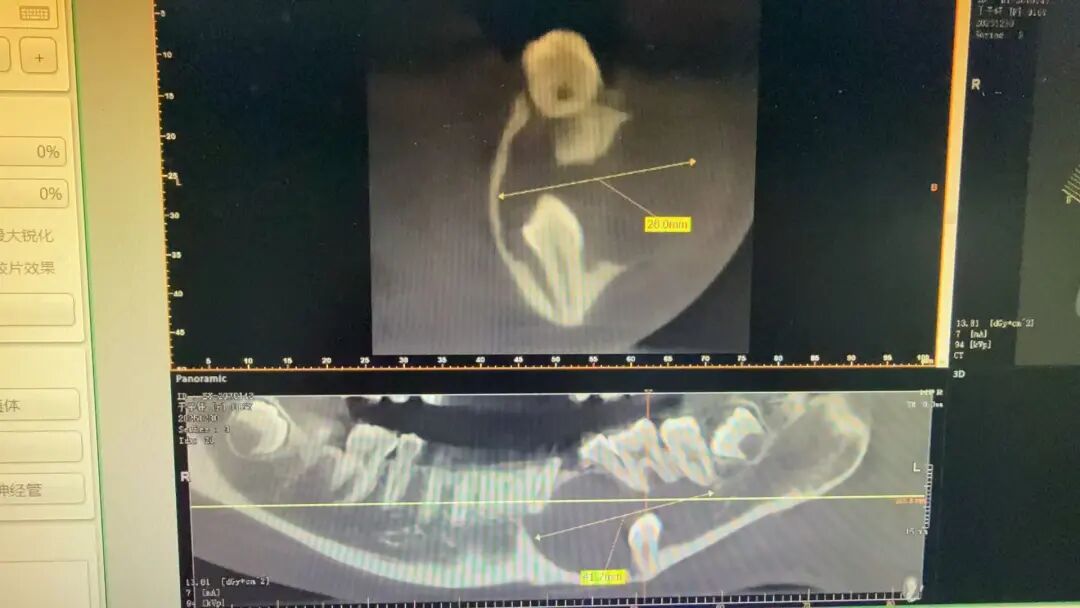

“孩子从没喊过牙疼,左脸突然肿了,以为是普通发炎,随便吃点药就能好,没想到拍片后才知道,里面藏着一颗牙,还长了这么大的囊肿!”期末考试刚结束,晶晶妈妈就带着孩子焦急地找到宁波市第二医院口腔颌面外科副主任徐斌主任医师。经详细检查发现,晶晶下颌骨底部“藏”着一颗牙,下颌骨内的囊肿已达41.7mm×26mm,牢牢压迫着5颗恒牙的牙根,恒牙健康岌岌可危。

当时的影像

“这颗埋伏牙藏在牙槽骨里多年,长期隐匿未被发现,慢慢引发了囊肿,再不及时手术干预,不仅这5颗恒牙保不住,颌骨也会受到不可逆的损伤。”听了医生的话,晶晶妈妈愈发慌乱:“如果尽快手术的话,孩子的5颗牙还能保住吗?”